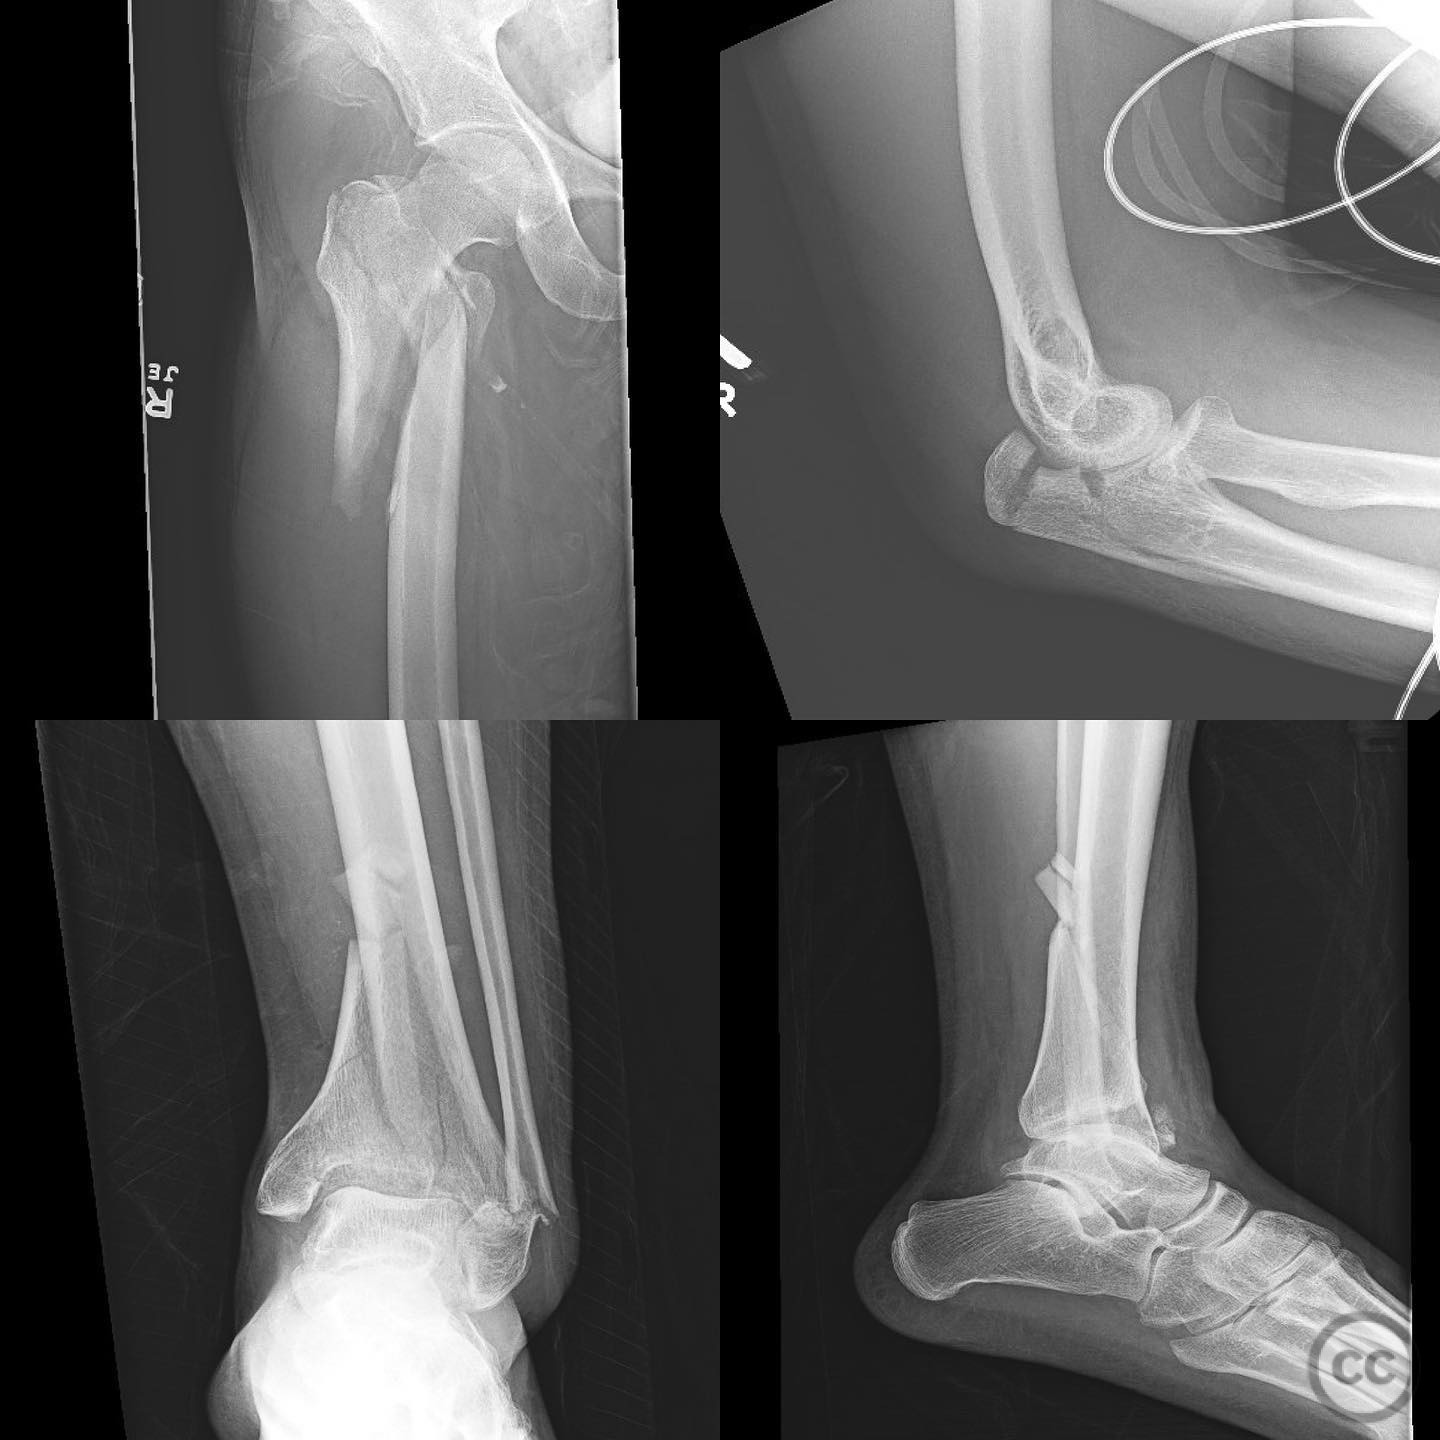

Polytrauma Management with Femur, Pilon,...

Seattle, United States

Ulna - AO/OTA 2Ux